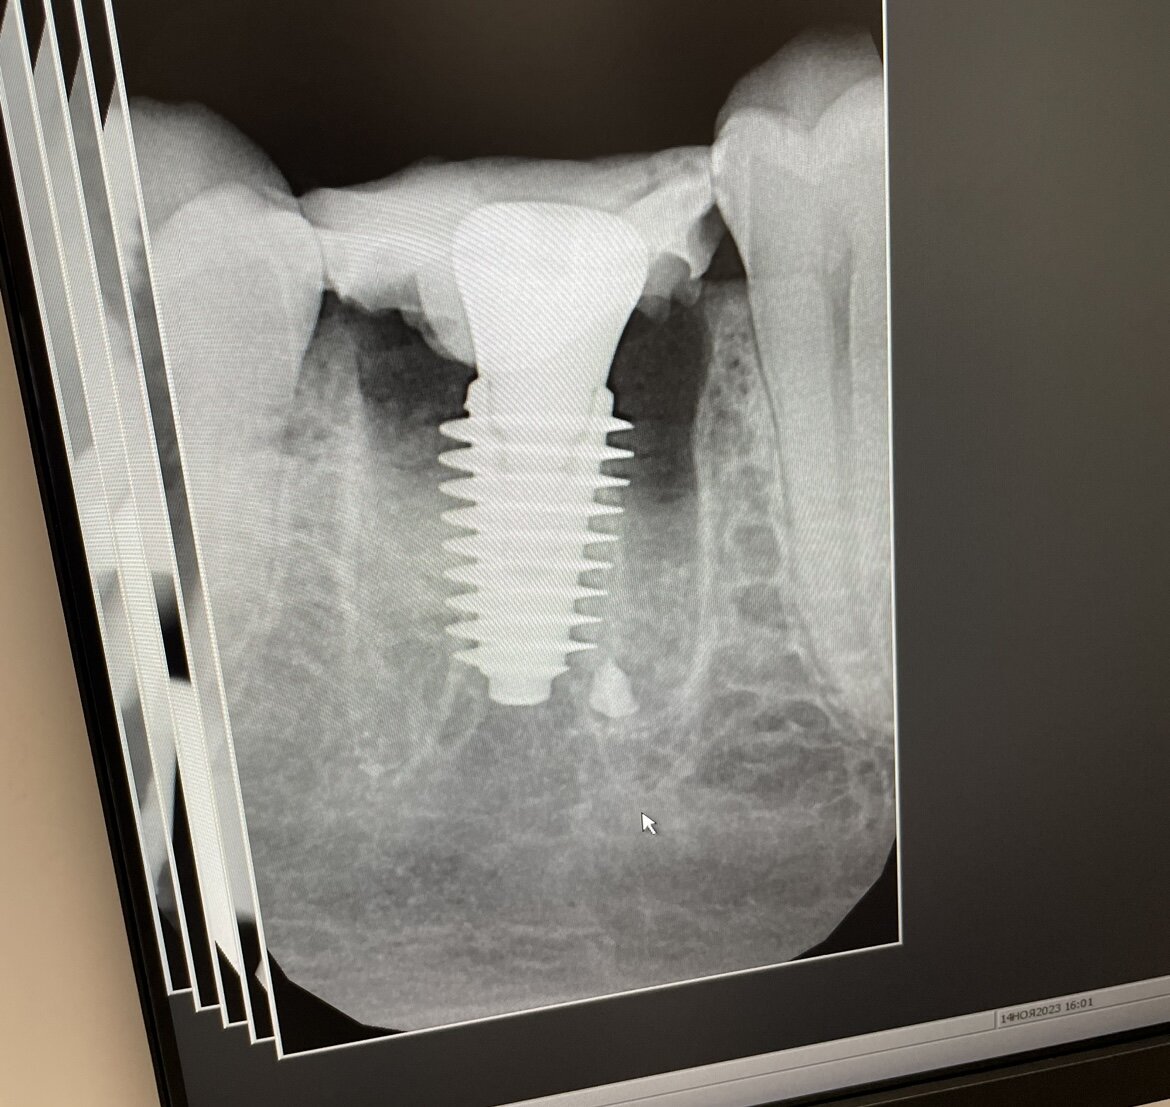

Вот он, корейский красавец.

В итоге минут через 40 зуб он удалил. И как-то молниеносно поставил имплант. По крайней мере я даже не поняла в какой момент он это сделал. Видимо находилась под впечатлением от процедуры удаления.

Сейчас план такой. Через неделю мне надо показаться на прием. Через месяц на имплант установят временную коронку и так я буду ходить какое-то время (месяца 3). А потом уже постоянную циркониевую коронку, либо керамику. Решу позже.